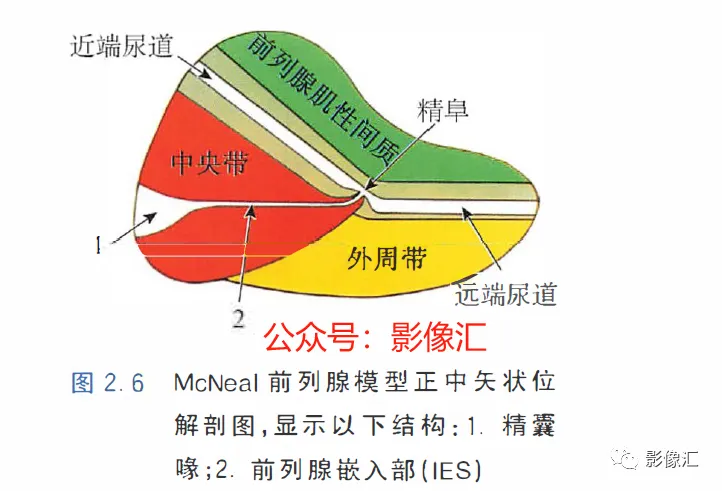

McNeal解剖模型认为前列腺根据周围不同结构环绕的关系而分为四个区域。尿道是描述整个前列腺区域解剖结构的解剖学标志。尿道由近端和远端尿道两个部分组成,每个部分约15mm长,由精阜分界。在精阜处,近端和远端尿道的走行呈35°。尿道壁由纵向走行的平滑肌纤维组成。围绕该内层的纵向肌肉层,是一层环形走行的肌层。两层平滑肌构成所谓的尿道内括约肌(IUS),其从膀胱颈延伸到尿道膜部的末端。IUS在膀胱颈的近端水平处最厚,随其向尿道膜部延伸,厚度逐渐减小。尿道膜部完整地被IUS环绕。在其前侧,前列腺内的lUS与前列腺肌性间质(AFMS)融合。两射精管走行方向与远端尿道平面平行,其开口于尿道腔内的前列腺小囊。移行带在前列腺组织中约占5%,构成两叶分别位于近端尿道两侧。其导管系统平行于尿道平面走行,止于精阜,射精管开口的近侧。移行带毗邻外周带,中央带和前列腺肌性间质,构成所谓的外科手术包膜,也就是说,确定了前列腺剜除术的外科手术平面。移行带和尿道周围腺体组织是良性前列腺增生(BPH)的发生部位。前列腺癌发生在移行带的比例为10%~20%。中央带在前列腺腺体组织中约占25%。其在前列腺底部形成金字塔形或锥形结构,在精阜水平处变窄至顶点。中央带的导管在射精管开口的两侧呈放射状走行。精囊和输精管穿入中央带形成射精管形似“精囊喙”。此区域由于缺乏前列腺包膜而成为解剖薄弱区。与射精管延续的中央带及伴行的筋膜和淋巴血管组织称为前列腺嵌入部(invaginated extraprostatic space,IES)。这是另一个解剖学上的薄弱区域,因此中央带疾病容易沿此区域播散。中央带相对发病率较低,发生在中央带的前列腺癌占5%~10%。外周带和中央带之间缺乏解剖学屏障,同时由于IES的存在,意味着前列腺尖部发生的肿瘤很容易进展到前列腺底部,并可早期造成前列腺周围间隙结构的受累。外周带约占前列腺腺体组织的70%。其包括前列腺表面的外侧、背侧和尖部,以多变的方式向腹侧延伸,与前纤维肌性间质相延续。前列腺不具有通常意义上的包膜结构,表面有一层腺样间质被称为“包膜"。前列腺“包膜”本身由纤维肌性间质构成,其在腺体周围形成一薄层结构。前列腺尖部没有这种间质层,造成一个解剖学上的蒲弱区域,称为梯形区域(trapezoidal area)。该区域腹侧以尿道膜部为界,背侧则以Denonvilliers和直肠筋膜为界,头侧以前列腺尖部(外周带)为界,尾侧则以直肠尿道肌为界。70%的前列腺癌发生在前列腺外周带。当前列腺癌起自前列腺尖部时,在早期即可通过梯形区域侵犯前列腺周围间隙。前列腺的背外侧神经血管蒂也是肿瘤易向外蔓延和侵袭的区域。AFMS约占前列腺体积的33%,是前列腺的非腺体区域,构成前列腺的前表面。在其最近端部分,其与逼尿肌和尿道内括约肌(IUS)的平滑肌纤维融合。头侧,其保持和尿道外括约肌(EUS)的关系;EUS的横纹肌纤维在该区域(前列腺尖部的前外侧)融合,构成前列腺外括约肌群。有四个“解剖薄弱“ 区域,通过这些区域,前列腺肿瘤可以生长并侵犯相邻的结构。这些区域是:精囊喙(图2. 6和图2. 17)

前列腺嵌入部(IES)(图2.6)

上图,前列腺中线正中矢状切面,显示中央带(CZ)、外周带(PZ)和前列腺肌性间质(AFMS)。注意在CZ底部的精囊喙水平缺少前列腺包膜。Denonvilliers筋膜由多个平行走行的鞘组成,头尾走行。在组织学上,其具有平滑肌纤维,血管和神经的纤维弹性结缔组织。在其侧缘,与Farabeuf骶骨-直肠-生殖-膀胱耻骨筋膜的外侧鞘及膀胱输精管动脉的横向隔膜融合。直肠-前列腺手术分离沿形成Denonvilliers筋膜的鞘复合体背侧进行操作。Denonvilliers筋膜是一层疏松的结缔组织。

AFMS:前列腺肌性间质;CZ:中央带;PZ:外周带;SV:精囊;IUS:尿道内括约肌。

根据示意图可显示五个筋膜(图2.16和图2.17)。上图,前列腺中线正中矢状切面,显示中央带(CZ)、外周带(PZ)和前列腺肌性间质(AFMS)。注意在CZ底部的精囊喙水平缺少前列腺包膜。Denonvilliers筋膜由多个平行走行的鞘组成,头尾走行。在组织学上,其具有平滑肌纤维,血管和神经的纤维弹性结缔组织。在其侧缘,与Farabeuf骶骨-直肠-生殖-膀胱耻骨筋膜的外侧鞘及膀胱输精管动脉的横向隔膜融合。直肠-前列腺手术分离沿形成Denonvilliers筋膜的鞘复合体背侧进行操作。Denonvilliers筋膜是一层疏松的结缔组织。

AFMS:前列腺肌性间质;CZ:中央带;PZ:外周带;SV:精囊;IUS尿道内括约肌。两个矢状面走行筋膜:Farabeuf骶骨-直肠-生殖-膀胱-耻骨鞘(左右各一);三个横轴面走行筋膜:脐-膀胱前筋膜;“生殖动脉隔”;直肠中动脉的隔(Septum of the mid-hae-morrhoiclal artery)。在前列腺,这些鞘也被称为“Retzius前列腺周围筋膜”“前列腺周围筋膜”“前列腺侧带”,或者最近称为“盆内筋膜腹侧面” 。这些筋膜覆盖腺体的侧面和腹侧,在腹侧与前纤维肌性间质(AFMS)融合。供血血管和支配神经在这些鞘内走行。一旦解剖前列腺后部或直肠前平面,这些鞘在前列腺的两侧形成手术分离平面。前列腺“本身”不具有包膜结构;所谓的包膜只是腺样间质聚集所致,而且个体间变异度很大,同时在某些点上并不存在,从而构成McNeal所述的解剖薄弱区域。因此,从实际的角度来看,我们认为虽然前列腺没有自己的包膜结构,但其确实有三个“假包膜":

- 识别解剖薄弱区域:①精囊喙;②前列腺嵌入部(IES);③前列腺蒂周围间隙;④梯形区域。